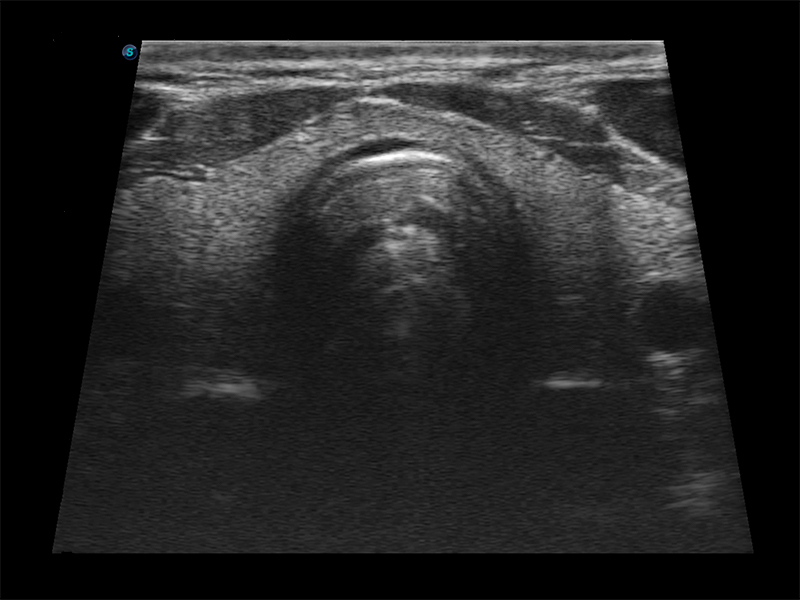

Aparat E1 to nowy model przenośnego, czarno-białego ultrasonografu, który wyposażono w bogaty pakiet funkcji wyróżniających go na tle konkurencyjnych modeli ultrasonografów klasy podstawowej. Aparat ten zapewnia użytkownikom nie tylko satysfakcjonującą jakość obrazów, lecz również usprawniony przebieg pracy.

Funkcja μ-Scan, redukcja szumu speklowego i wzmocnienie krawędzi

Obrazowanie złożone przestrzennie

Tryb PIH – obrazowanie harmoniczne z inwersją impulsu

Obrazowanie szerokokątne – powiększony obszar obrazu